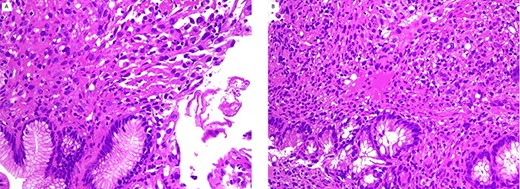

The polyps were received in formalin and measured between 0.4 and 0.6 cm. A paraffin-embedded tissue was sectioned at 3 microns and multiple levels were evaluated with routine hematoxylin and eosin stain. Microscopic examination revealed that most of the surface of this polyp was covered by normal but focally eroded gastric and colonic mucosa. The lamina propria was infiltrated by tumor cells that were arranged in solid nests with focus of glandular structures lined by single layer of cuboidal cells (Fig. 1). The tumor cells had rounded nuclei with fine chromatin and visible nucleoli. The cytoplasm was abundant and eosinophilic.

gastric (A) and colonic (B) polyps show neoplastic cells in lamina propria with normal mucosa (H/E stain ×200).